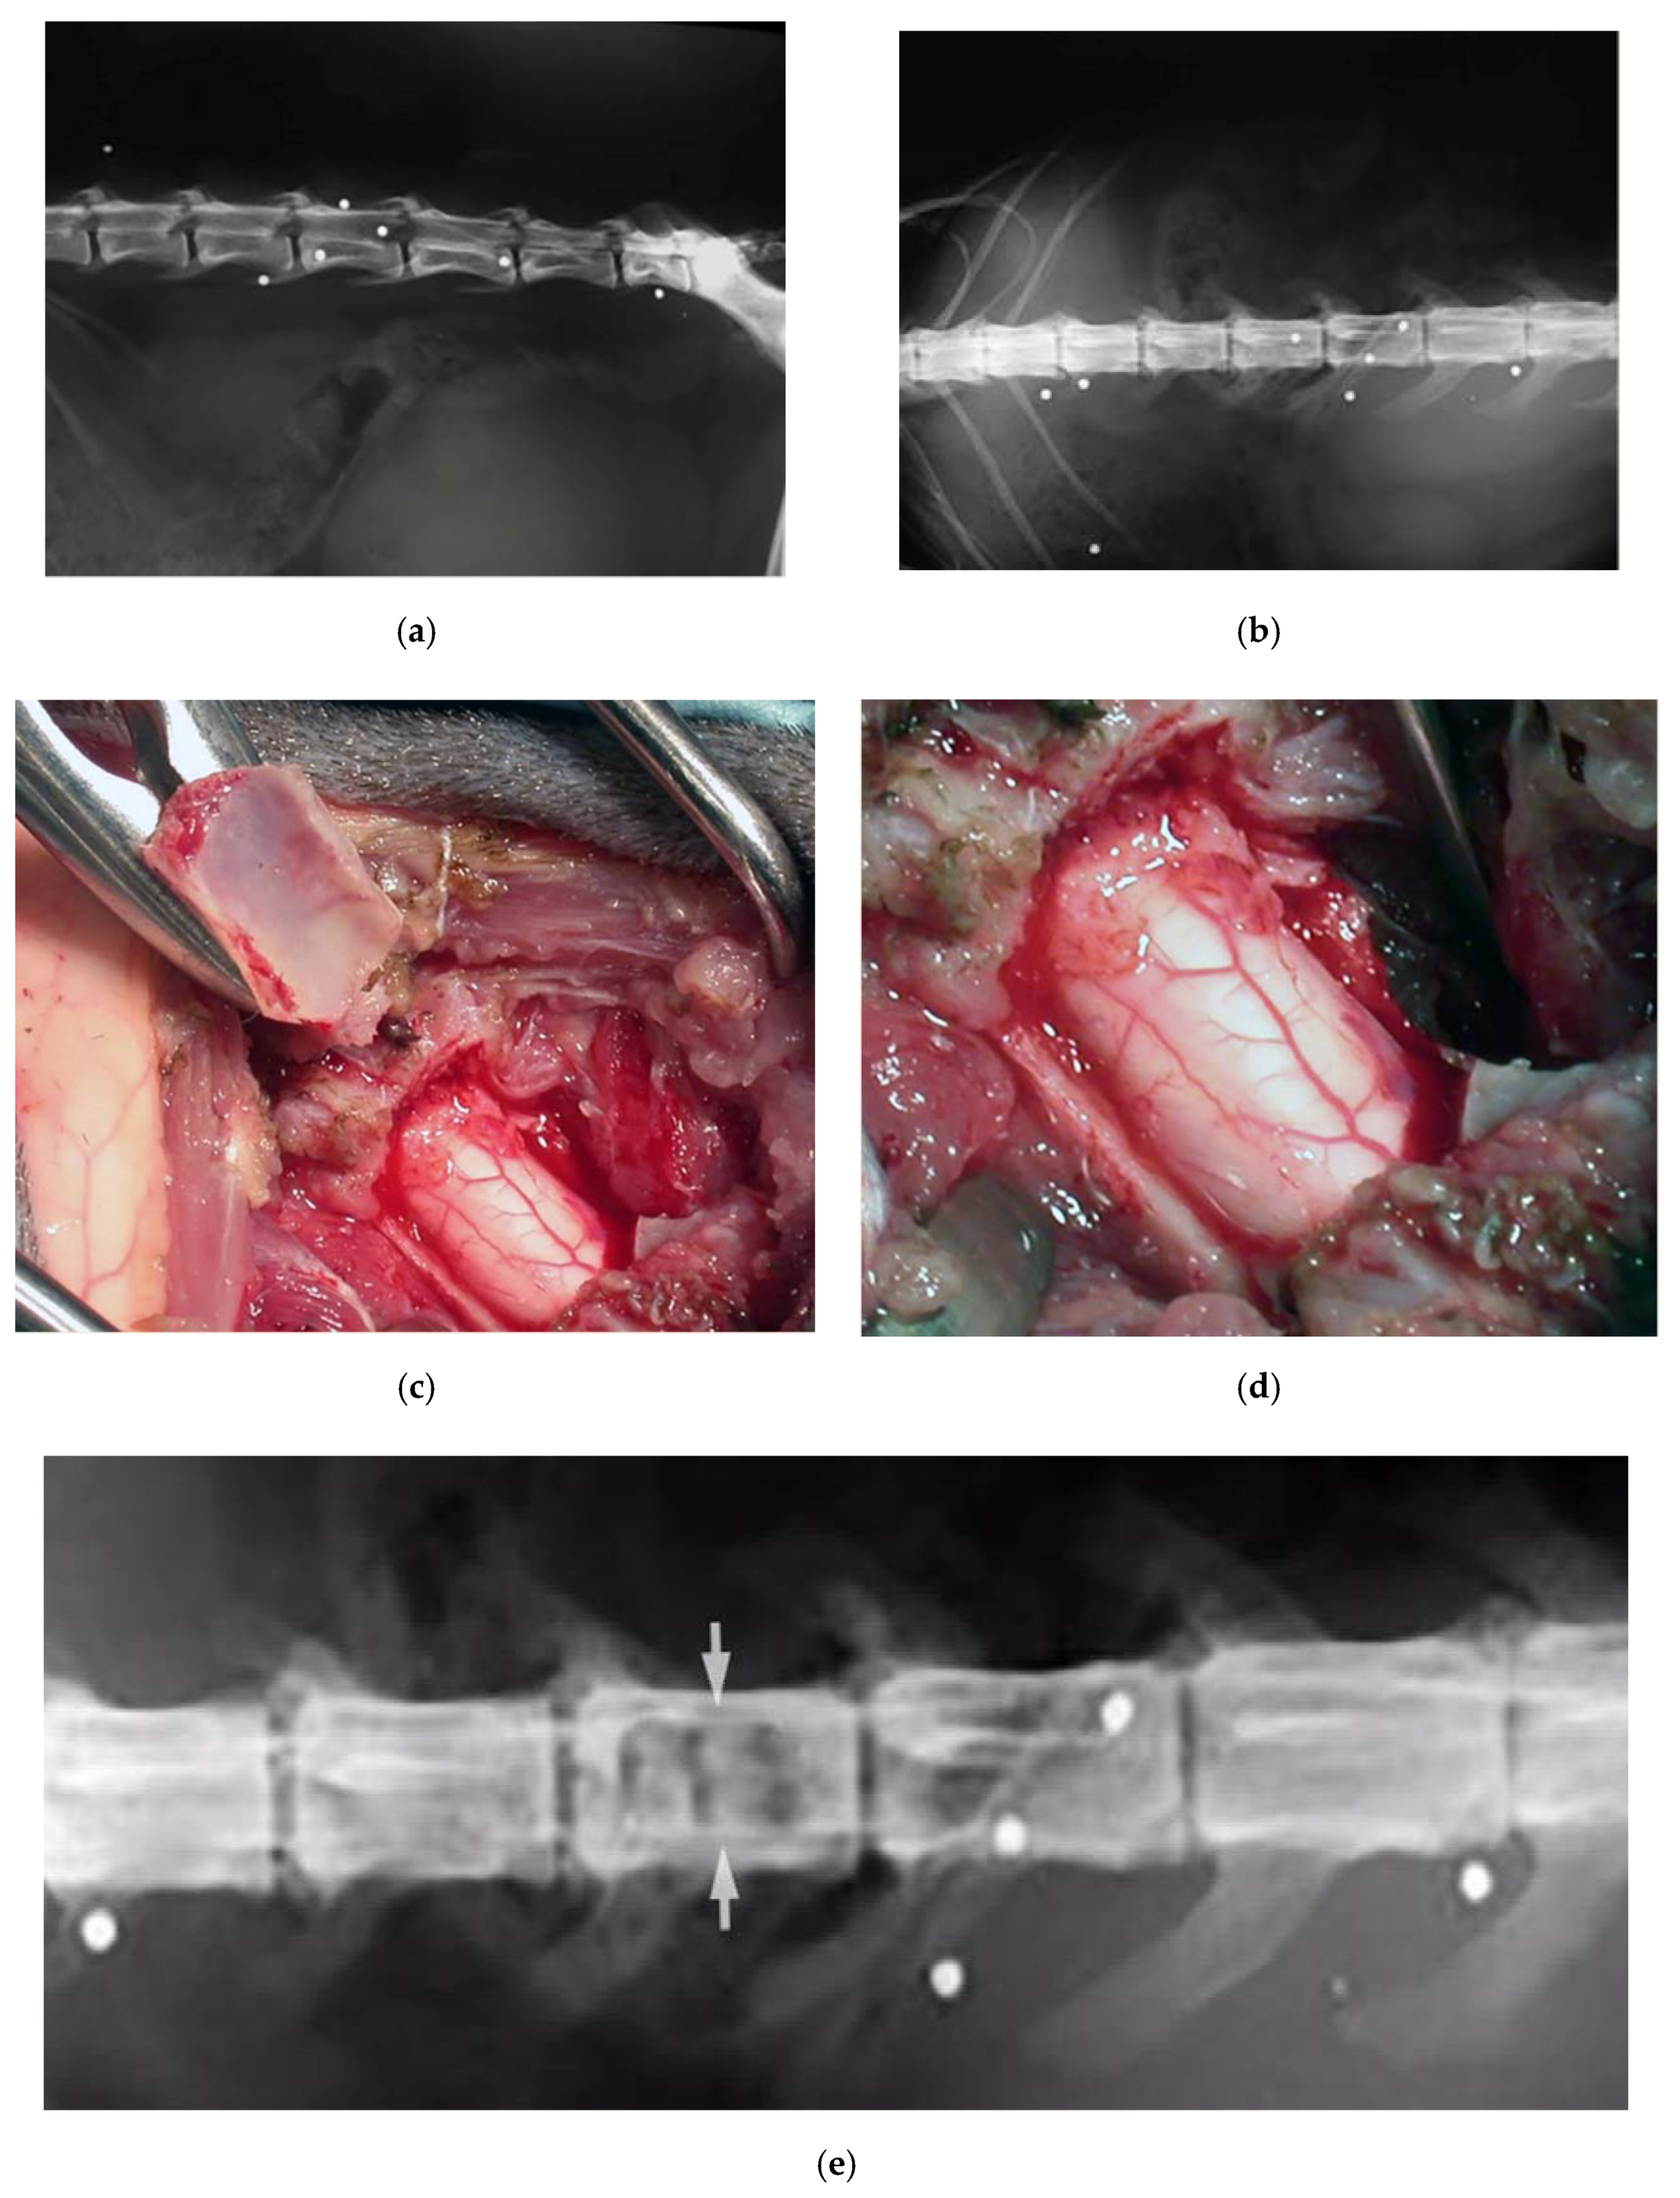

Dog, female, four years old, 0.8 kg, paraplegic, diagnosed with a T13-L1 fracture-luxation with hyperkyphosis secondary to a road accident. The dog underwent a thoracic laminectomy with a monolateral vertebral stabilization T13-L1 with plate and screws (Figure 5). By the six-month follow-up, the dog had partially recovered.

Figure 5.

X-ray showing a T13-L1 fracture with hyperkyphosis in a paraplegic dog (a). A safe thoracic piezoelectric laminectomy was obtained with an angled sharp tip (OT2, Osteotomy Tips Kit, Mectron Medical Technology, Genoa, Italy) piezoelectric bone scalpel (b). Dorsal monolateral vertebral stabilization T13-L1 with plate and screws. Noteworthy, piezoelectric scalpel with a different straight tip was used as tapper for the screws placement (c).

Cat, male, three years old, 3 kg. Firearm trauma with a secondary spinal cord compression due to a retained lead shot. The cat was paraplegic. He underwent to a laminectomy and spinal cord decompression by means of the piezoelectric bone scalpel, where, once again, it was possible to spare completely the spinal cord (Figure 8). Recovery was very fast, without complications.

Figure 8.

X-ray in latero-lateral (a) and ventro-dorsal (b) projection, showing multiple retained lead shots in a cat paraplegic because victim of a firearm trauma. One of the intrathecal lead shots caused a spinal cord contusion and partial compression. A subdural hematoma was also present. Intraoperative pictures showing lumbar spinal cord after decompressive one-level laminectomy performed with piezoelectric scalpel and an angled small saw tip (OT7S-3, Osteotomy Tips Kit, Mectron Medical Technology, Genoa, Italy) (c,d). Six-months postoperative ventro-dorsal X-ray showing the site of the laminectomy (e).